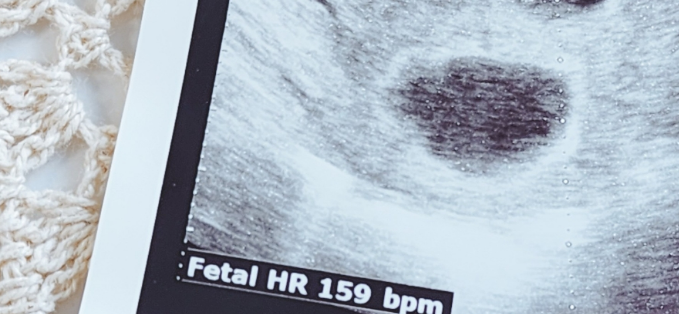

이 시기의 태아는 약 2.3~2.5cm 정도로 성장했으며,

초음파에서는 손과 발이 돋아난 모습,

머리와 몸통의 구분이 점차 또렷해집니다.

심장박동은 여전히 분당 120~160회로 빠르고 규칙적

손을 흔들거나, 팔다리를 움직이는 모습이 관찰되기도 함

질초음파를 통해 더 선명하게 관찰 가능

복부 초음파는 보통 11~12주 이후에 활용